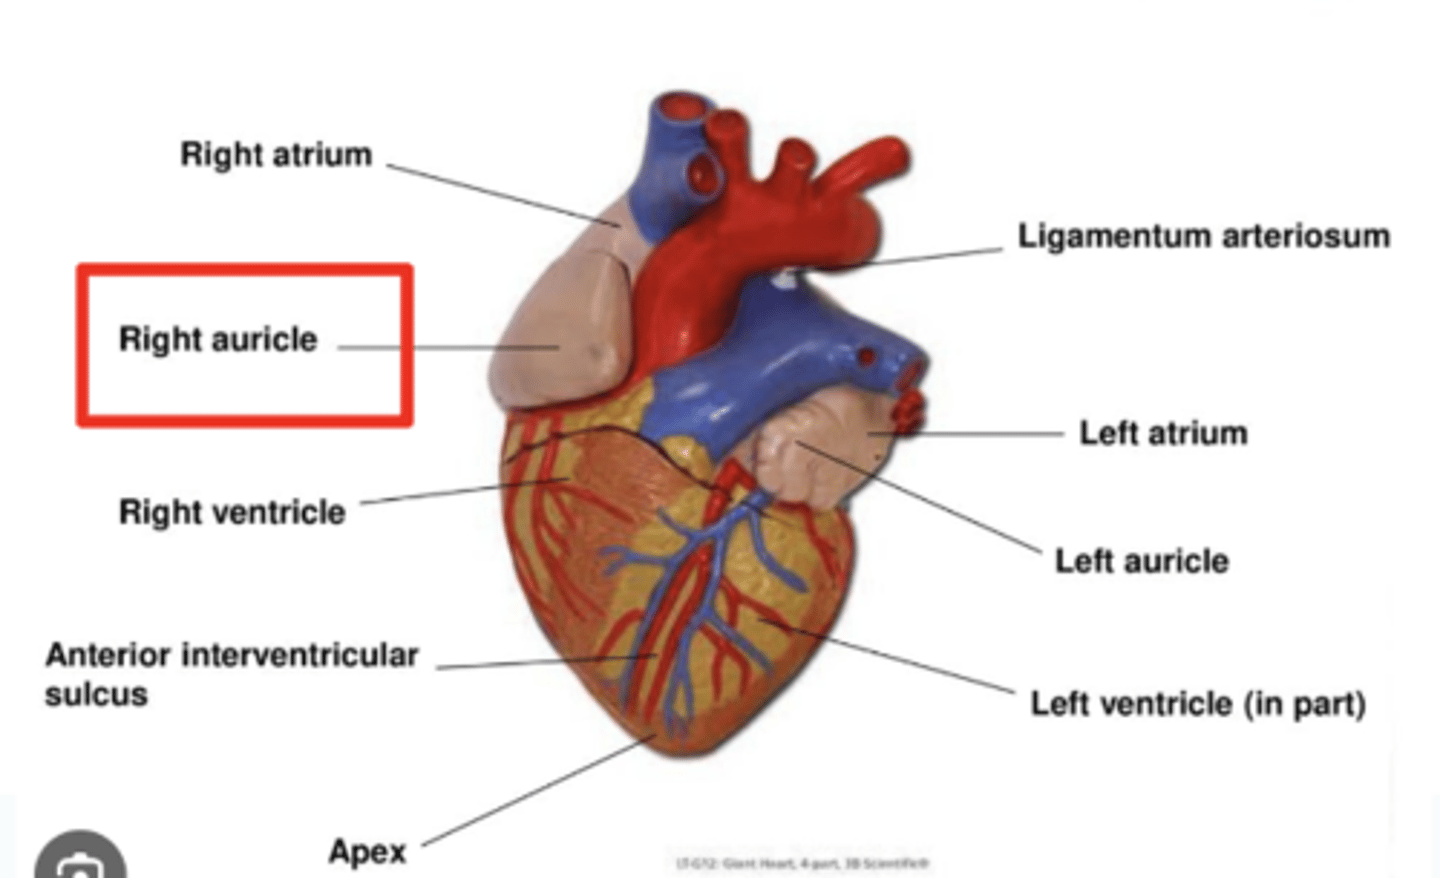

Describe the apex in the heart's anterior view

. Point to left side, downwards.

. At the level of the 5th intercostal space (we will auscultate the apex of the left ventricle)

Describe the Sternocostal Surface

Most of the anterior surface of the heart corresponds to the right ventricle.

What are the atrial appendages?

Rough trabeculated region of the atria (Extensions of the atria)

External portions of the atria, (Real cavities of the right and left atrium being posterior to these auricles)

ALSO CALLED AURICLES

Describe the location of the main arteries in the anterior view of the heart

The pulmonary trunk exits the right ventricle

. aorta exits the left ventricle.